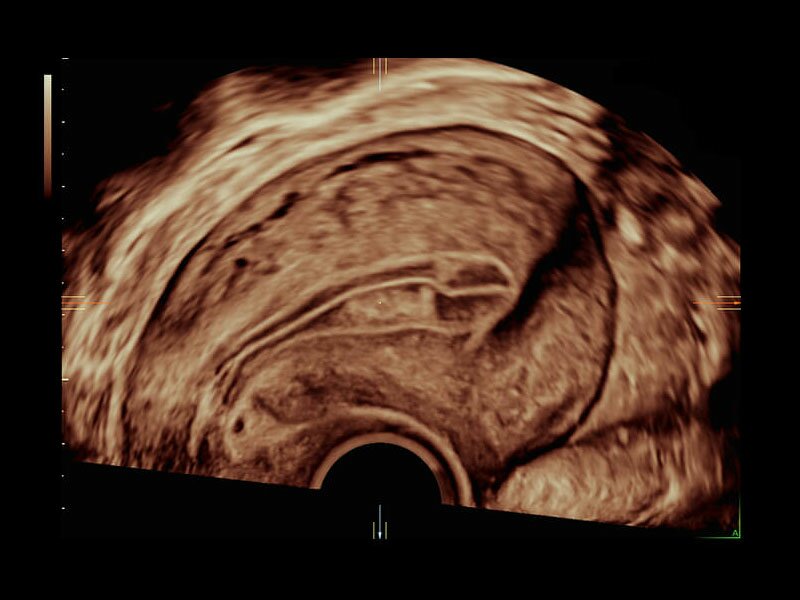

Клинические изображения

Объемное сканирование Voluson — 3D/4D вашей мечты

Объемное УЗИ на Voluson E10 — это не просто потрясающе красивая картинка, это ценный инструмент получения дополнительной информации при обследовании женщин.

Voluson E10 поддерживает инновационные технологии формирования изображений — HDlive Silhouette и HDlive Flow, которые позволяют увидеть мельчайшие детали. Алгоритм SonoRenderlive упрощает рабочий процесс и дает возможность реконструировать изображение поверхностей, определяя область перехода между тканью и жидкостью.

Инновационная технология визуализации HDlive обеспечивает получение реалистических изображений за счет эффекта объемного зрения, повышая достоверность клинической оценки. Теперь режим HDlive дополняют две новые функции:

• Технология HDlive Silhouette — задает разный уровень прозрачности, помогая выявлять контуры внутренних структур и точнее оценивать состояние плода в первом триместре.

• Технология HDlive Flow — повышает реалистичность визуализации сосудистых структур, улучшая восприятие глубины (по сравнению с традиционным цветовым допплером и функцией HD-Flow).